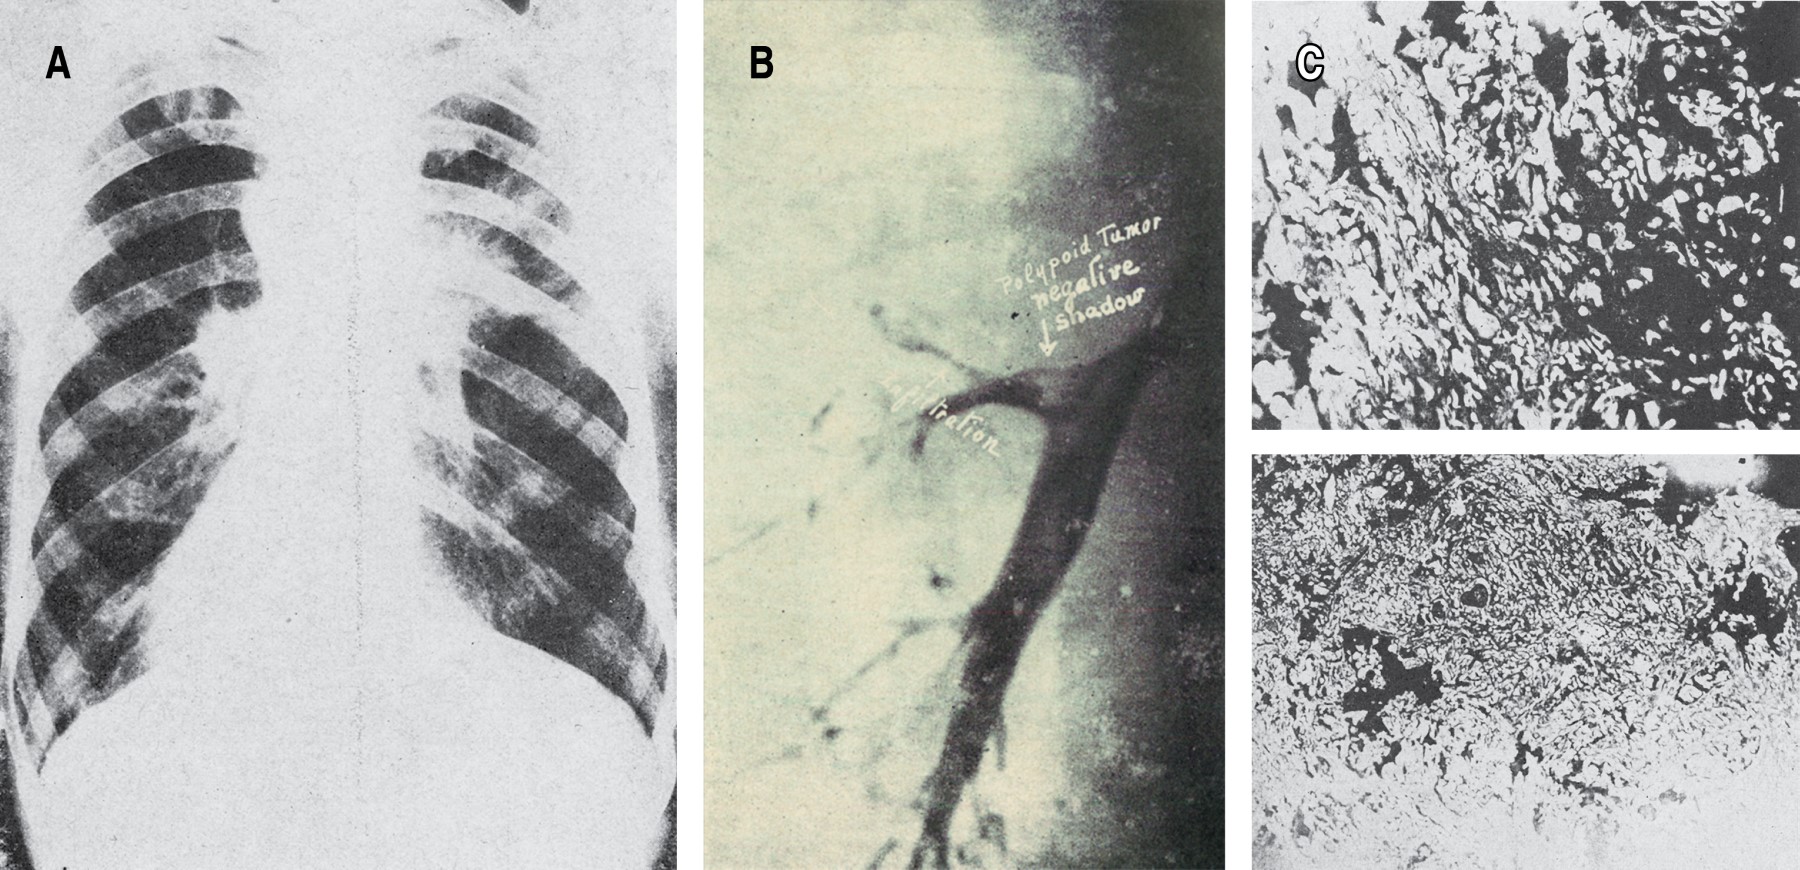

El primer artículo publicado en NCT que hace referencia específica y directa a la imagenología de tórax se titula "Estudio radiológico del cáncer pulmonar", de los doctores Alejandro Bandala y Alejandro Celis, publicado en el tercer número de la revista en 1939.2 Este artículo describe el uso de las proyecciones oblicuas y laterales en el diagnóstico de cáncer pulmonar, sus estrategias para el diagnóstico del derrame pleural concomitante, seguido de la neumoserosa con contraste, una técnica en la cual se instilaba material de contraste en la pleura con el objetivo de descubrir el proceso neoplásico subyacente (Figura 1). En 1940, el doctor Pedro L Fariñas de la Habana, Cuba, publica en NCT una conferencia dictada durante el Curso de Tuberculosis para Posgraduados del Sanatorio de Huipulco (INER) titulada: "Recientes progresos en el examen broncográfico del carcinoma primitivo del pulmón"; hace una descripción detallada de la broncografía, como único método para obtener información sobre la localización y extensión de las neoplasias pulmonares (Figura 2),3 con una amplia recomendación del estudio y hace uso de un léxico coloquial que permite entender el contexto humanista para su realización. El Dr. Fariñas describe en detalle: es esencial en la evaluación radiomorfológica y radiofisiológica; la broncografía con contraste brinda información explícita; hace referencia semiológica de la diseminación hemática, por contigüidad y linfática de las neoplasias pulmonares; narra la técnica de anestesia de la vía aérea, la introducción del catéter que permitía llegar al hemitórax a evaluar, con el paciente en decúbito lateral a explorar y la instilación del material de contraste (llamados aceites yodados o soluciones orgánicas de yodo), así como la toma de placas de "acecho" en el momento conveniente; discute sus desventajas; y, describe la correlación broncográfica con el análisis histopatológico.